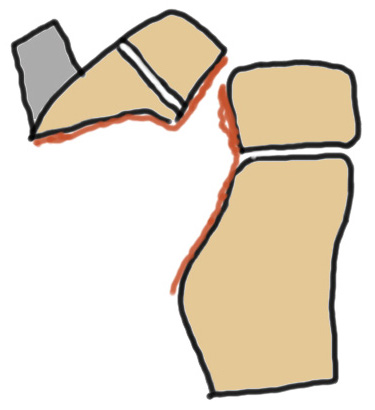

Ogden Classification

A: Undisplaced

B: Displaced

| Type I | Type II | Type III | Type IV |

|---|---|---|---|

| Avulsion distal tibial tubercle | Extension into tibial physis but not into knee joint | Extension across tibial physis and into knee joint | Extends posteriorly across tibial physis |

| Disrupts extensor mechanism | Disrupts extensor mechanism |

Disrupts extensor mechanism Disrupts articular surface Disrupts growth plate |

Disrupts extensor mechanism Disrupts articular surface Disrupts growth plate |

|

Associated Osgood-Schlatter Second most common |

Most common Risk of compartment syndrome |

Risk of compartment syndrome |

Type IB

Type IIB

Type III

Comminuted Type III